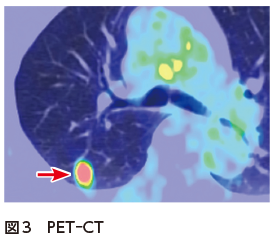

胸部単純X線写真では右中肺野に右第7肋骨に重なって楕円形の結節影を認めた(図1).胸部CTでは右上葉S2の葉間胸膜直下に13 mmの境界明瞭な円形の結節を認めた.内部の濃度は不均一で,血管収束像や分葉状の辺縁は認めなかった(図2A,B).PET-CTでは同部位にSUVmax 12.56のFDG集積を認めた(図3).腫瘍マーカーは正常であった.CTでbronchus sign陽性の気管支は存在しなかったため,気管支鏡検査は施行せず,肺がんcT1bN0M0 StageⅠA2疑いとして診断・治療目的で右肺S2区域切除術を施行した.病理検査では多数の多核巨細胞を含む組織球が集簇した肉芽腫性の病変を認め,一部に変性壊死を起こしていた.Grocott染色で組織球に貪食される無数の酵母状真菌が観察され,肺クリプトコッカス症の診断となり,手術で病変は切除できているので無治療も選択肢だったが,患者と相談し,フルコナゾールの内服を開始した.

肺クリプトコッカス症はクリプトコッカス属真菌による感染症である.感染すると組織球が活性化して肉芽腫が形成され,真菌を封じ込める.CTでは肉芽腫形成を反映した結節を認める.同一肺葉内に多発する場合もあるが,本症例のような孤立性結節は,原発性肺がんとの鑑別が難しい.肺クリプトコッカス症のCT所見の特徴として,境界明瞭,胸膜直下が好発部位,空洞形成を伴うことがある,などがあげられる.しかし,spiculation,胸膜嵌入像,末梢血管の収束像,PET-CTでのFDG集積といった肺がんと酷似する所見を示すこともある1)